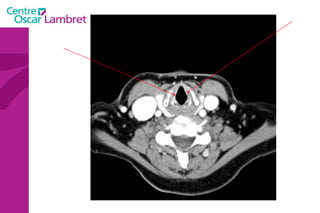

Les  artères Carotides Communes  : La droite vient du TABC. La gauche vient de la crosse de l’aorte. Elles n’ont aucune branche collatérale. L’appareil circulatoire

L’artère carotide primitive droite : Elle naît à 3 cm en arrière de l'articulation sterno-claviculaire à la hauteur de T1. monte dans la gouttière carotidienne le long de la trachée et du corps thyroïdien, de l'oesophage puis du larynx et du pharynx.  Elle s’évase avant sa terminaison en regard du bord supérieur du cartilage thyroïde et de C4.  L’appareil circulatoire

L’artère carotide primitive gauche  : naît directement de la crosse aortique et comporte un premier segment intra thoracique en arrière du manubrium sternal. Son segment cervical est identique à celui de la carotide primitive droite.  L’appareil circulatoire

Artères sous-clavières  : l’une à droite et l’autre à gauche. La droite naît du tronc brachio-céphalique moins longue que la gauche, elle se dirige obliquement en haut et en dehors.  La sous-clavière gauche, au contraire, naît directement de l’aorte, remonte verticalement en haut. Arrivées au niveau de la première côte, ces deux artères présentent la même disposition, deviennent horizontales, passent entre les deux muscles scalènes et prennent le nom d'axillaires.

L’artère vertébrale  : Elle naît de la sous-clavière pré-scalénique et chemine verticalement sur 25 cm environ.  On lui décrit 4 segments. L’appareil circulatoire

L’artère mammaire interne  : naît de la face inférieure de la sous-clavière, un peu en dehors de la vertébrale. Elle épouse la partie antérieure du dôme pleural et descend verticalement à la face profonde du plastron costal à 1 ou 2 cm en dehors du bord latéral du sternum.  L’appareil circulatoire